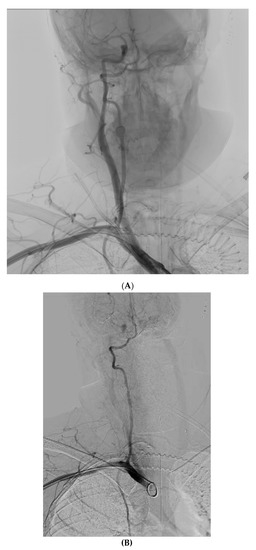

4. Case 3

Figure 3. (A) Contrast extravasation from the left SCA, after closure device failure. (B) Manual compression with balloon assisted inflation at the site of the extravasation. (C) Final result, with no extravasation.